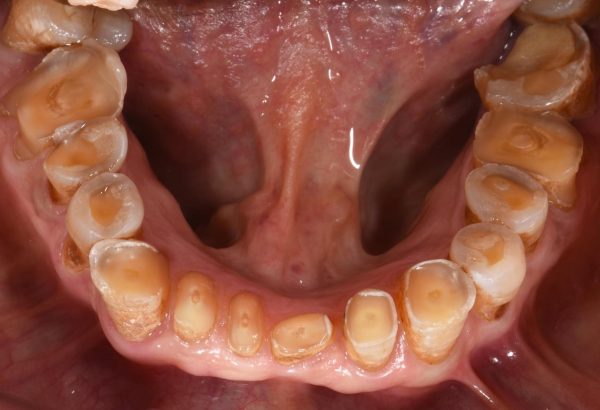

Digital Smile Designing is a cutting-edge dental technology that allows us to digitally plan and visualize your ideal smile before any treatment begins. Using high-resolution images, facial analysis, and advanced software, we design a smile that harmonizes perfectly with your facial features, personality, and expectations.